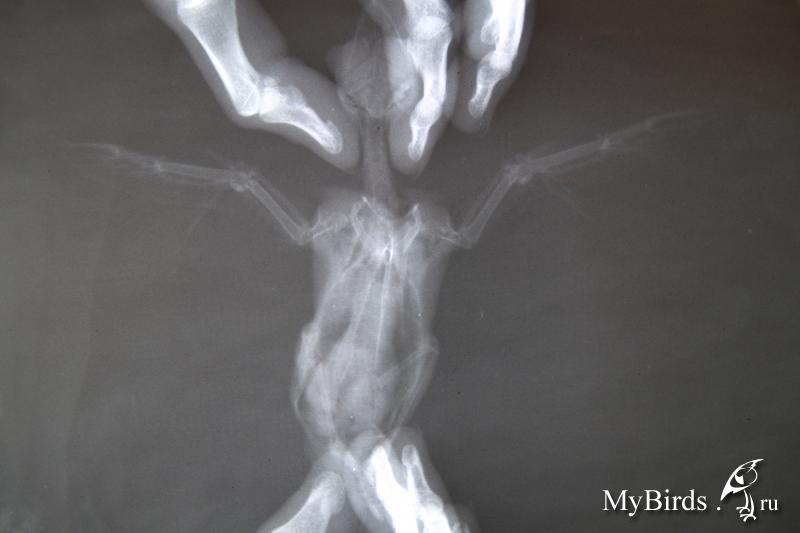

Здравствуйте. Прошу помощи специалиста в расшифровке рентгена.

У стрижа ранка на левом крыле. В ветклинике сказали, что переломов нет.

Прописали «Левомеколь». Есть сомнения, что нужно мазать. Перья у потенциально летного стрижа пачкать не хотелось бы.